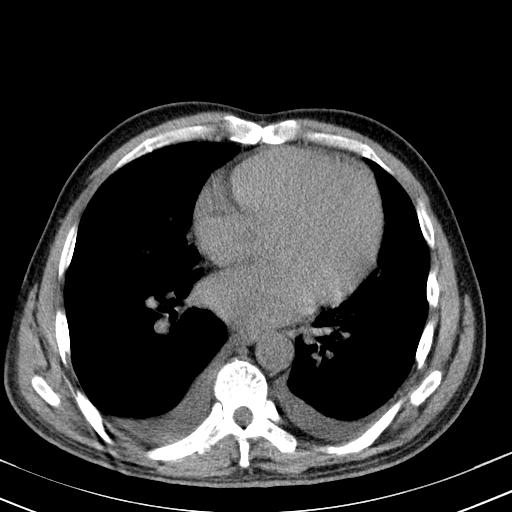

以下是引用zjzjr在2010-3-21 17:39:00的发言:[br]右下中心型肺癌并阻塞性肺炎/不张,纵膈淋巴结肿大,右侧大量胸腔积液,左侧少量胸腔积液

以下是引用zxl51642在2010-3-21 17:06:00的发言:[br]右下中心型肺癌并阻塞性肺炎/不张,纵膈淋巴结肿大,右侧大量胸腔积液,左侧少量胸腔积液,少量腹水。建议纤维支气管镜进一步检查。